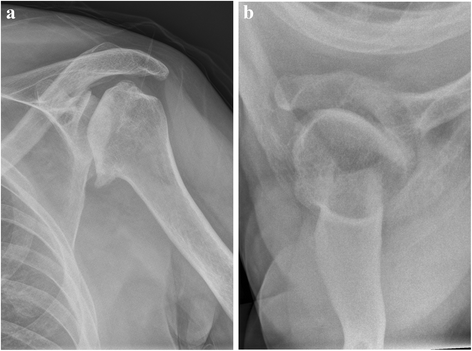

Background: Arthroplasty is a proven treatment option for glenohumeral osteoarthritis. Common indications include primary or posttraumatic osteoarthritis, avascular necrosis of the humeral head, rotator cuff tear arthropathy and rheumatoid osteoarthritis. Arthroplasty is rarely performed among patients with glenohumeral dysmelia. An overuse of the upper limb in patients with thalidomide-induced phocomelia and people with similar congenital deformities like dysmelia results in premature wear of the shoulder joint. This study aims to evaluate our experience with cases of glenohumeral osteoarthritis caused by dysmelia and treated with arthroplasty. To date, few reports on the outcome of shoulder arthroplasty exist on this particular patient group.

Case presentation: We included four dysmelic patients (five shoulders) with substantial glenoid dysplasia in a prospective database after approval by the local ethics committee. Once conservative treatment options had been exhausted, the patients were treated with shoulder arthroplasty and assessed clinically and radiographically before and after surgery. The mean patient age at the time of surgery was 50.4 years. The minimum follow-up time was 24 months (24-91 months). All patients experienced a considerable improvement of range of motion (ROM) and a relief of pain. No intra- or postoperative complications appeared.

Conclusion: Patients with dysmelia have acceptable short and mid-term results with resurfacing hemiarthroplasty. It is an effective although somewhat complicated method to relieve pain and improve movement. Long-term performance of arthroplasty in patients with dysmelia remains to be seen, particularly with regard to the remaining problem of the altered and often deficient glenoid.